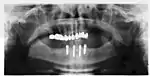

Success or failure of implants depends primarily on the thickness and health of the bone and gingival tissues that surround the implant, but also on the health of the person receiving the treatment and drugs which affect the chances of osseointegration. The amount of stress that will be put on the implant and fixture during normal function is also evaluated. Planning the position and number of implants is key to the long-term health of the prosthetic since biomechanical forces created during chewing can be significant. The position of implants is determined by the position and angle of adjacent teeth, by lab simulations or by using computed tomography with CAD/CAM simulations and surgical guides called stents. The prerequisites for long-term success of osseointegrated dental implants are healthy bone and gingiva. Since both can atrophy after tooth extraction, pre-prosthetic procedures such as sinus lifts or gingival grafts are sometimes required to recreate ideal bone and gingiva.

The long-term success of implants is determined, in part, by the forces they have to support. As implants have no periodontal ligament, there is no sensation of pressure when biting so the forces created are higher. To offset this, the location of implants must distribute forces evenly across the prosthetics they support.[28]: 15–39 Concentrated forces can result in fracture of the bridgework, implant components, or loss of bone adjacent the implant.[29] The ultimate location of implants is based on both biologic (bone type, vital structures, health) and mechanical factors. Implants placed in thicker, stronger bone like that found in the front part of the bottom jaw have lower failure rates than implants placed in lower density bone, such as the back part of the upper jaw. People who grind their teeth also increase the force on implants and increase the likelihood of failures.[15]: 201–208

When a more exacting plan is needed beyond clinical judgment, the dentist will make an acrylic guide (called a stent) prior to surgery which guides optimal positioning of the implant. Increasingly, dentists opt to get a CT scan of the jaws and any existing dentures, then plan the surgery on CAD/CAM software. The stent can then be made using stereolithography following computerized planning of a case from the CT scan. The use of CT scanning in complex cases also helps the surgeon identify and avoid vital structures such as the inferior alveolar nerve and the sinus.[31][32]: 1199